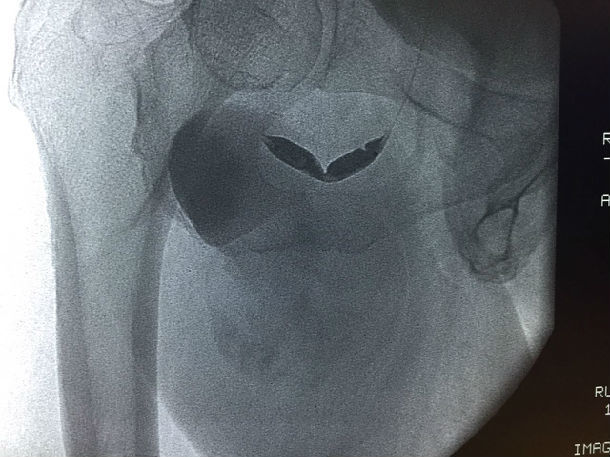

入院后查体:患者右腹股沟下1cm处可见一搏动性包块,6*9cm,边界清楚,质偏软,表面无红肿及淤血,表面皮肤完整,无破溃。

超声提示:右侧腹股沟区见假性动脉瘤形成伴附壁血栓形成,囊性包块6.5*10.3cm,与髂外动脉相同,可见红蓝相间的血流信号。

春节将至,能否给患者和医务人员的我们一个满意的答卷呢?周全的手术方案和万全的准备是必须的。看似简单的股深动脉瘤,确实是对我们技术的严峻挑战。分析病例我们不难发现该病例的一些特点:如果我们采用传统的外科手术方式是较为安全的,但是其中潜在的问题,如开刀风险、手术创面大,术后淋巴管漏等并发症较多,另外术后恢复时间较长,在这特殊时间内对患者来说并不是最好的选择。有没有更简单、经济、创伤较小的方法呢?经讨论后提出多种手术方案:最理想治疗是用小型覆膜支架封堵瘤体口,但是,根据患者下肢血管CTA提示,该患者髂动脉严重迂曲,成角偏小,右侧髂动脉迂曲成直角,入路困难,另覆膜支架顺应性差,植入困难,费用也较大,作为备选方案。如果用传统单纯的弹簧圈治疗,巨大假腔,费用大,疗效不确切,并且有可能会有远期不适,也列入备选方案。还有就是经左侧穿刺,翻山至右侧股深动脉,小球囊封闭瘤体口,经球囊向瘤体内注射凝血酶,待自身形成血栓后,释放球囊,用2枚裸支架覆盖瘤体口,这样既减少创伤,减少费用,同时可防止瘤体内血栓脱落至股深动脉,此手术方案较为理想。那么实际操作中会是怎样的结果,我们无法预知,充足的术前准备显得尤为重要。入路的选择:患者高度肥胖,股动脉穿刺困难(脂肪厚股动脉触摸困难,穿刺要求很高,一旦出问题后果不堪设想)。支架的选择,我们联系多方厂家备用所有可能会用到的支架,介入治疗失败或是操作受限后外科的手术也全部就位。2016-02-03手术在计划中进行,患者体型肥胖,股动脉触摸困难,穿刺就是一个挑战,凭我们丰富的经验,一针见血,穿刺成功通过,更严峻的挑战还在后面,置管造影显示,患者髂动脉严重迂曲,多处迂曲近直角,所有的操作都需谨慎小心,防止导管打折、断裂,引起出血,另多次在各个分支和假腔血管间选择,假腔内操作容易导致瘤体破裂,造成大出血,技术难度大。手术紧张而有序,反复确认瘤体开口口径及有无流出道后,球囊顺利送达瘤体口内,经球囊注射凝血酶,能否形成血栓,大家拭目以待。20min过去了,透视见瘤体内预先残留的造影剂不再消失,自身血栓形成,看到了成功的希望,由于患者动脉迂曲严重,翻山鞘管规格有限,覆膜支架顺应性差,鞘管支撑力不够,经各位医生讨论后,决定用2枚裸支架代替,精确定位后,顺利释放支架,复造影见支架位置良好,贴壁良好,无明显血流渗入瘤体,瘤体搏动消失。患者目前恢复良好,预计可以在春节前2天回家过年。

本次手术巧妙采用球囊阻断瘤口,用凝血酶促进自体血栓形成的办法,为患者省钱近10万元。我们用智慧、爱心、责任给患者一份厚礼!